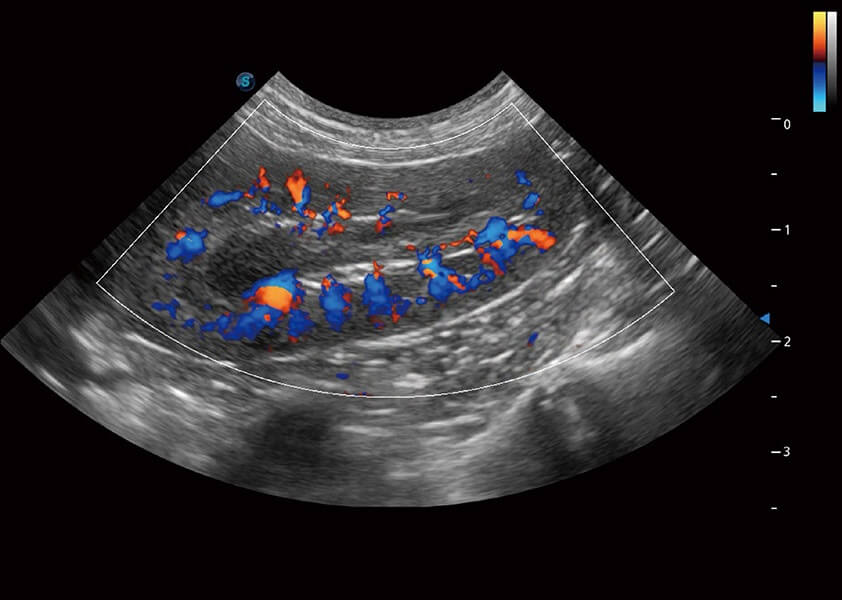

ProPet 60 作为一款高端台式动物超声设备,为动物医生的日常诊断提供了一系列贴合动物临床需求、解决临床实际问题的高级成像功能。凭借全系列高清探头,满足医生对腹部、心脏、生殖、浅表、肌骨等成像的所有需求,切实帮助您提升检查效率,提高诊断信心。

动物是人类最亲密的朋友和最值得信赖的伙伴。1xBET也一直致力于探索动物专用的超声影像解决方案。 全新推出的ProPet系列,是1xBET在动物超声影像智能化、专业化、精准化的一次跨越式革新。动物不能用言语来表述自己的不适,通过超声影像,ProPet系列搭建了动物医生与不同物种沟通的“桥梁”,为动物医生注入了“治愈之力”。